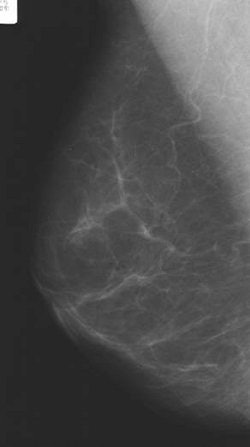

Mammograms from the National Health Service Breast Screening Programme were used as a baseline measure, with follow-up imaging done a year later. Warren and Sala assigned Wolfe patterns, and visually estimated the percentage density of each set of mammograms.

| Women taking an isoflavone tablet daily for one year showed a changeover to a more lucent Wolfe pattern on mammography. The differences between the treatment group and the placebo group were not statistically significant (p = 0.31). All images courtesy of Dr. Ruth M.L. Warren. |

The results showed there was no difference in estimated percentage density at baseline, mean of 61.8% according to Warren and 61.6% based on Sala's read, or follow-up (58% and 57.4%, respectively). Mammographic density did decrease in both groups, but the difference between treatment and placebo was not statistically significant, the authors wrote.

According to Warren's read, 22% of the women in the isoflavone group changed to a more lucent Wolfe pattern versus 18% of the placebo group. There was no change for 78% and 80%, respectively, and only a 2% change to a denser Wolfe pattern in the placebo group.

According to Sala's read, 15% of those taking isoflavones exhibited a more lucent Wolfe pattern compared to 19% in the placebo group. Eighty-four percent of the women on isoflavones showed no change, as did 80% of the women taking the placebo. Finally, only 2% of both groups showed a denser Wolfe pattern.